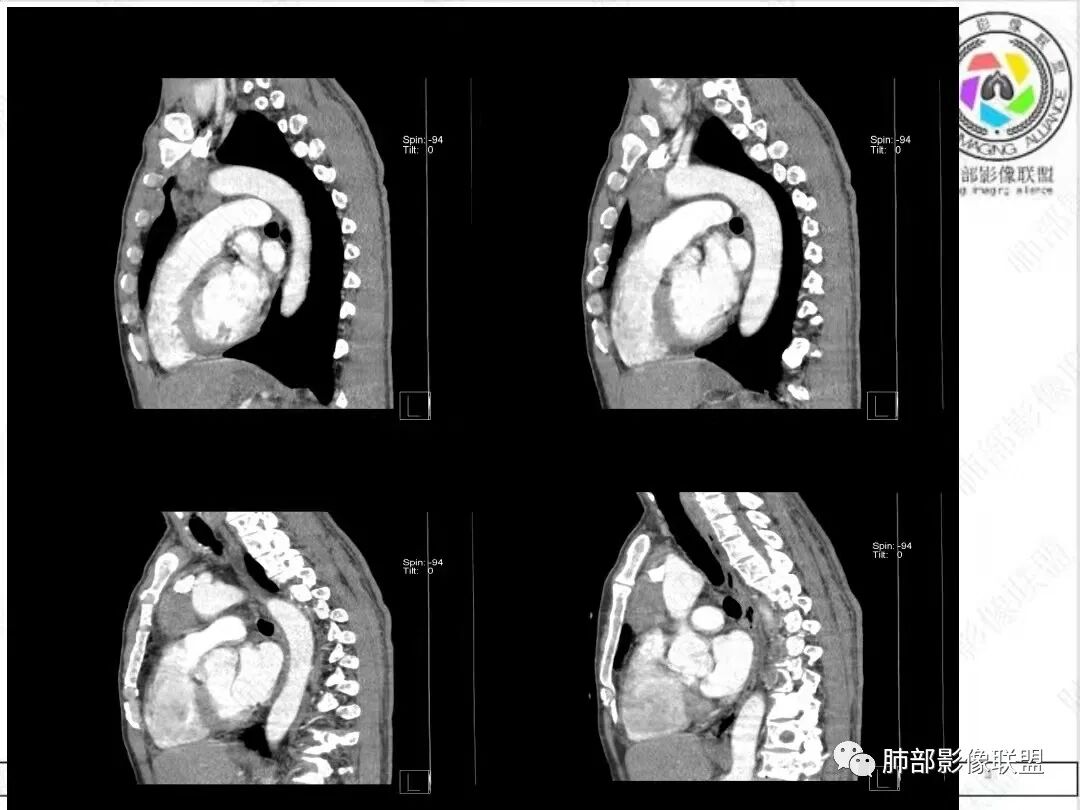

2、影像特点:胸部CT:平扫,前纵隔肿物,基本居中,与周围结构局部分界不清。增强后显示轻中度强化。肿块沿血管间隙侵袭性生长,左无名静脉受压明显变形受侵。纵隔、右肺门多处大小不等淋巴结,左侧内乳淋巴结稍增大。右侧瘤肺交界面光滑,左侧凹陷,肺组织未见明显受侵。右肺中下叶可疑小结节。胸椎及肋骨骨质增生性破坏。肋骨骨折。

病理结果:胸腺不典型类癌。

3、病例小结:  病人以胸痛就诊,无明显内分泌症状;前纵隔该部位肿瘤,胸腺瘤常见,乳酸脱氢酶偏高,55岁的年龄也较符合胸腺瘤,但胸腺瘤较少侵犯甚至包绕大血管生长、少有淋巴结肿大。

很多老师提到前纵隔占位+血管肿块内漂浮+内乳淋巴结增大+轻中度强化=淋巴瘤,淋巴瘤确有上述特点,但本例血管漂浮不明确,病灶强化不均匀,胸椎及肋骨可疑增生性转移,应想到胸腺癌或不典型类癌的可能性。